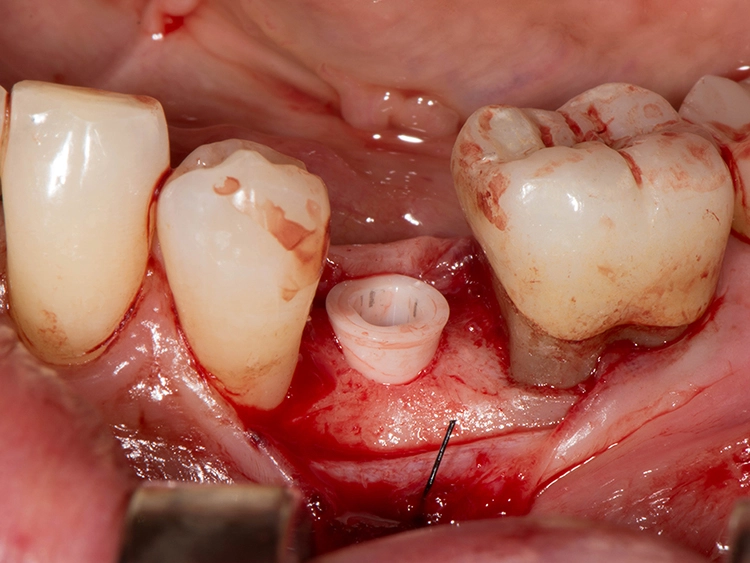

Sie bieten Vorteile, „wenn gleichzeitig eine Knochenaugmentation geplant ist und das Implantat nicht mit einer hohen Primärstabilität inseriert werden kann. Das kann im Frontzahnbereich sein, wenn eine laterale Knochenaugmentation erfolgen soll. Das gilt aber ebenso für den Seitenzahnbereich, wenn gleichzeitig ein Sinuslift durchgeführt wird, wo wir Höhe aufbauen und wir eine unerwartete Überbelastung verhindern wollen“, beschreibt der erfahrene Oralchirurg und erklärt: „Dann sind zweiteilige Implantate einfacher in der Anwendung, weil das Abutment nicht in die Mundhöhle hineinragt und daher eine ungewollte frühzeitige Belastung verhindert werden kann. Außerdem stellen zweiteilige Implantate bei zahnlosen Patienten eine verlässliche Option dar.“

Zweiteilige Implantatsysteme würden darüber hinaus mit einer höheren prothetischen Flexibilität punkten, weil die Aufbauten individueller gestaltet werden können. Dr. Röhling: „Das kann ein Vorteil sein, wenn etwa die prothetische Achse korrigiert werden muss.“ Hinzu kommt, dass bei Anwendung von zweiteiligen Systemen eine Zementierung, die für Fehlerquelle anfällig gesehen wird, entfällt, da sie eine reversibel verschraubte Befestigung erlauben, während bei einteiligen Implantaten die Suprakonstruktion nur zementiert gestaltet werden kann (siehe Fallbeispiel, Abbildungen 1 bis 10).